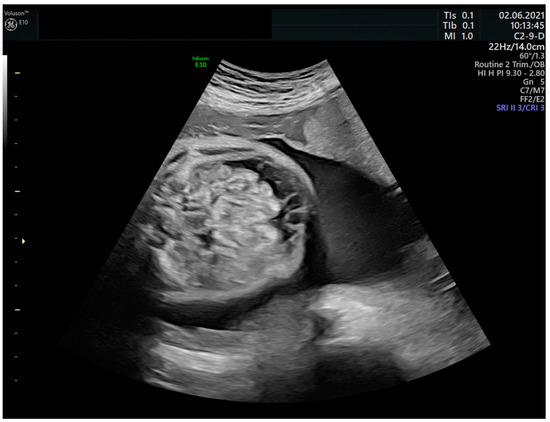

Fetuses with sustained or severe tachyarrhythmia end up suffering heart failure and fetal hydrops as a pathophysiological representation [27,28], which is reached in 30–40% of fetuses with SVT and 7–43% in those with atrial flutter (AFL) [14,29] (Figure 2). In the absence of treatment, intrauterine death occurs in up to 9% of cases [30].

Figure 2.

Fetal ascites in the context of hydrops due to fetal tachyarrhythmia.

Prenatal conversion of arrhythmia, a relevant determinant of postnatal outcome, is more frequent in the absence of fetal hydrops, with fetal hydrops being considered one of the main factors affecting the effectiveness of treatment [14,31]. In fact, numerous studies have shown that fetal hydrops are an independent predictor of treatment failure, concerning less placental transfer and increased fetal volume of distribution due to the aforementioned mechanism [3].